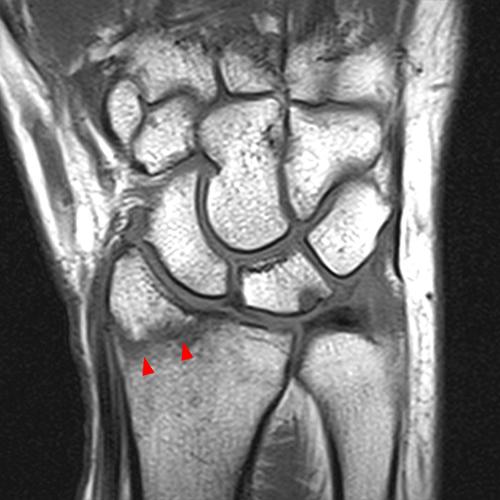

Clinical History: A 68-year-old female presents with radial-sided pain and swelling. Axial T1-weighted (1A), axial fat-suppressed proton density-weighted (1B), and coronal fat-suppressed proton density-weighted (1C) images are provided. What are the findings? What is your diagnosis?

Figure 2: The axial T1-weighted (2A), axial fat-suppressed proton density-weighted (2B), and coronal fat-suppressed proton density-weighted (2C) images demonstrate a thickened extensor retinaculum, surrounding soft tissue edema, and fluid signal in the first extensor compartment of the wrist (arrowheads). Marrow edema is noted within the subjacent radius (asterisks). A single extensor pollicis brevis and two abductor pollicis longus tendon slips are present with heterogeneous intrinsic signal.